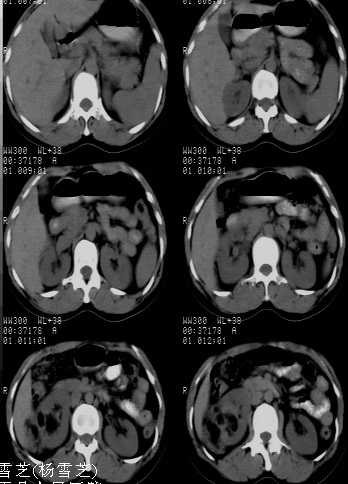

标题: CT24780:女 41岁 右肾多发低密度占位性病灶 [打印本页]

标题: CT24780:女 41岁 右肾多发低密度

女 41岁 超声检查:右肾多发实质性包块,性质待查(提示:错构瘤或其它病变),临床病史不详。